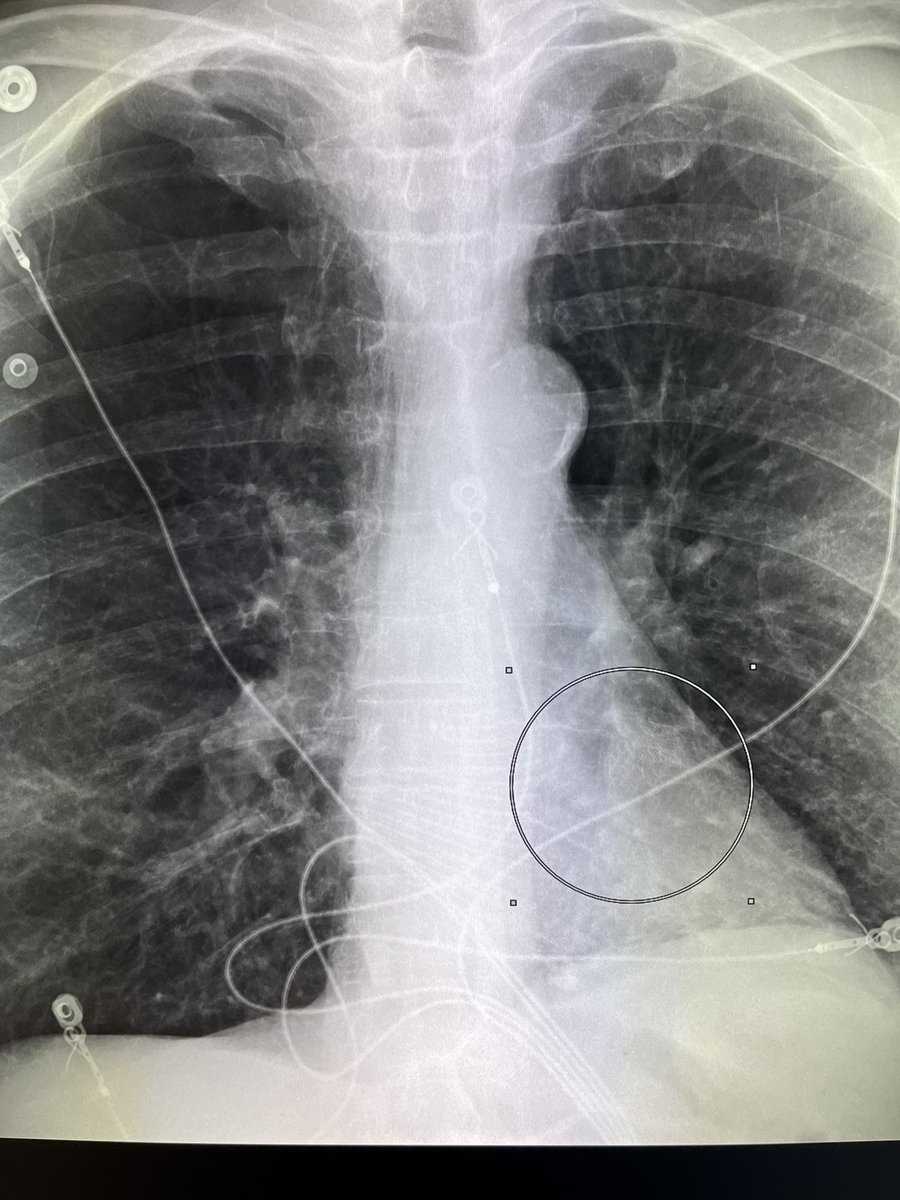

Look closely !! What is expected as left atrial occlusion device is actually is “endobronchial valves “ be careful do not generalize. #radres #radiology

Look closely !! What is expected as left atrial occlusion device is actually is “endobronchial valves “ be careful do not generalize. #radres

#radiology